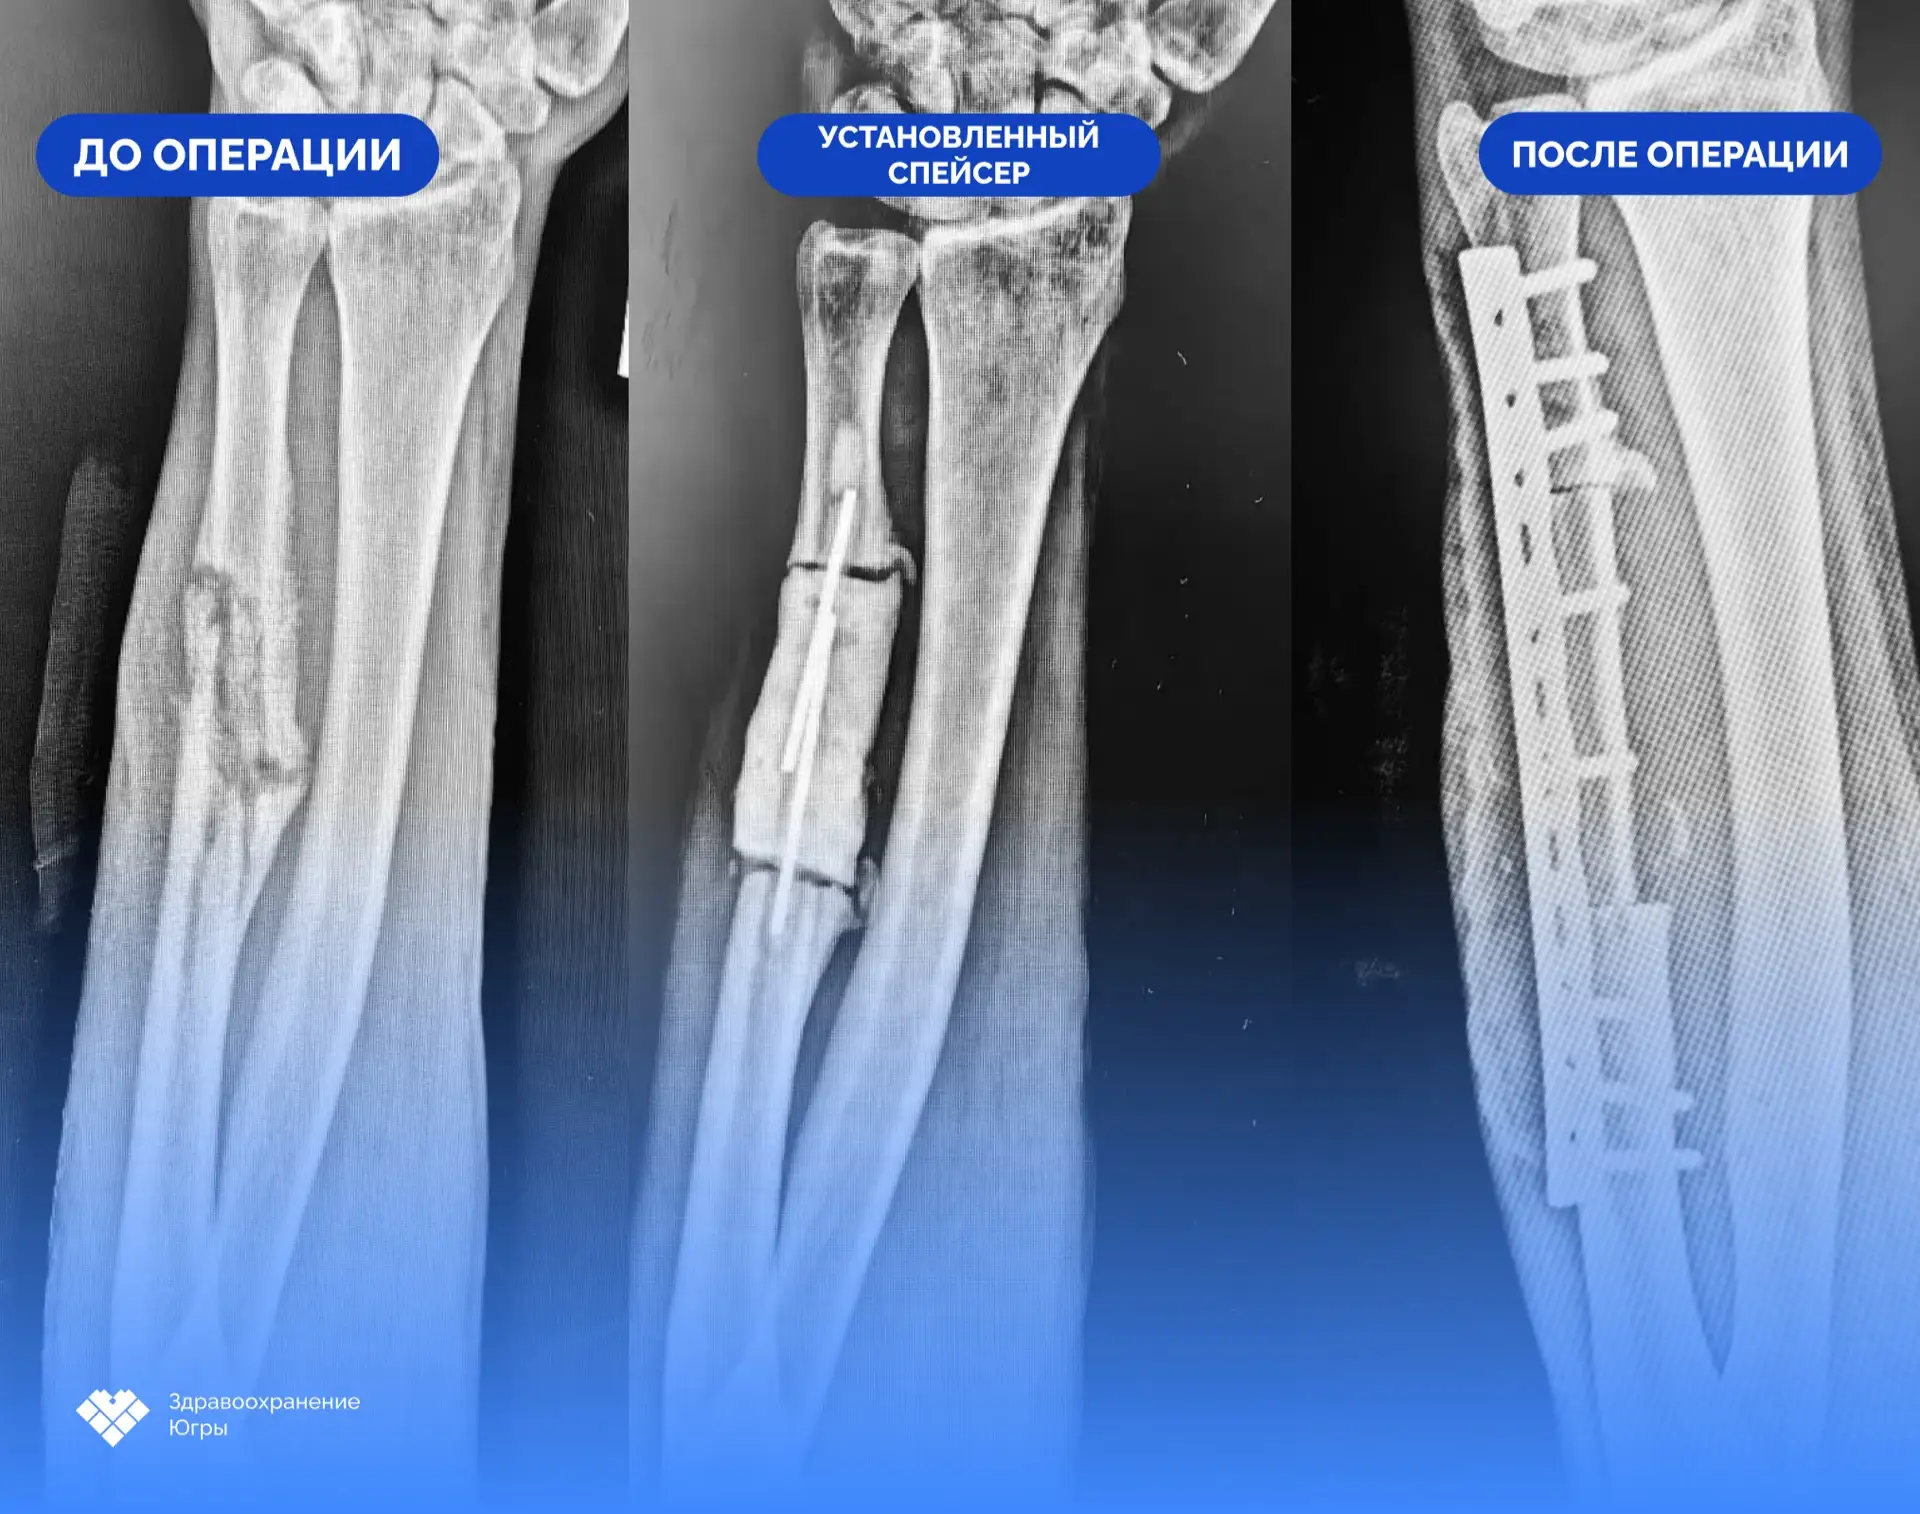

После проведенного дообследования принято решение об этапном хирургическом лечении. В первую очередь выполнена санация очага инфекции, удалена нежизнеспособная костная ткань. В результате операции образовался дефект локтевой кости протяженностью 6 сантиметров. Для его замещения был установлен антибактериальный спейсер – временный цементный эндопротез с добавлением антибиотика. В течение двух месяцев он поддерживал кость, сохранял длину предплечья, а также боролся с инфекцией.

При повторной госпитализации пациента контрольные исследования показали, что воспалительный процесс купирован. Травматологи-ортопеды удалили спейсер и приступили ко второму этапу лечения – костной пластике. С применением микрохирургической техники врачи выделили фрагмент малоберцовой кости вместе с сосудистым пучком и пересадили его в зону дефекта. Сосудистый компонент трансплантата был совмещен с локтевой артерией и получил местное кровоснабжение. Это создаёт дополнительные благоприятные условия для регенерации и более прогнозируемого сращения перелома. Завершилась операция установкой накостной пластины, которая будет обеспечивать надежную фиксацию.